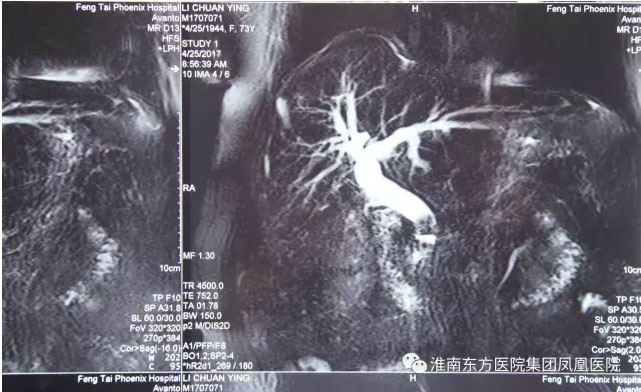

凤台县刘集乡75岁女患者李某,十年前因胆囊结石曾做过胆囊切除手术。十年后,李某再次因腹痛发热住进了我市市区一所大医院,诊断为胆总管多发结石,最大结石直径已经接近1.5cm。因该院不具有ERCP技术,只能建议李某再次实施传统的开刀手术取石。由于李某年事已高,且十年前已经做过胆囊切除手术,再次手术不仅风险大,成功率也会相对降低。家属通过多方打听后,决定将李某转入我市ERCP技术最棒的东方医院继续治疗。

经过精心的术前各项准备工作,上午9点,手术按预定时间正式开始,张军主任在台上实施,江永强院长亲自在监视器前指挥作战。仅仅20多分钟后,患者胆总管结石被顺利地全部取出,手术完美收官。